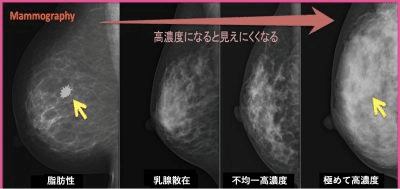

2つ目は、日本人に多いと言われる乳腺組織が多い高濃度乳房(デンスブレスト)の場合、がんが見えづらいという問題が解決していない点です。検出率が半分となるClass D(Class 4)の高濃度乳房は、最新のマンモ(トモシンセシス、3Dマンモ)でも解決できていません。また、ご自分が高濃度乳房かどうかを受診者が知らされないことも多いんです。

マンモグラフィー検査を受けても、日本人は高濃度乳房が多いため、がんを見逃されやすいという難点をよくご存知の方のなかには、検査を受けても仕方がないと考えてしまう場合もあるようです。

超音波検査(エコー)を併用すれば高濃度乳房でもがんを発見できる率は高まりますが、日本では超音波検診を担当する技師の数が足りていないため、高濃度乳房をすべての受診者に通知することには慎重な意見があり、まだ通知する制度やきまりはありません。